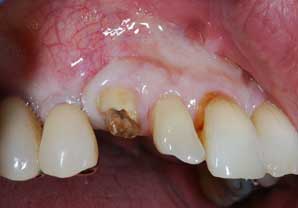

IMPIANTI POST-ESTRATTIVI

Impianto post-estrattivo

In un paziente cardiopatico di 72 anni